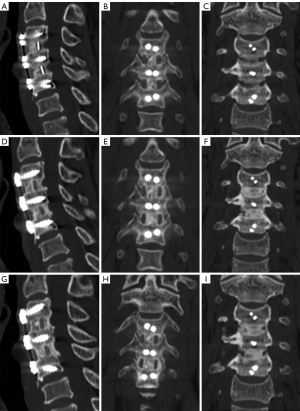

Radiological outcomes: disc height, segmental stability, and subsidence

Both groups showed significant improvements in mean disc height and segmental height postoperatively (P<0.05), with no significant differences between groups at any time point (P>0.05; Table S3). The subsidence rate was similar in both groups (autograft group: 38.8%; allograft group: 36.5%; P>0.05). No cases required reoperation, and no new radiographic foraminal stenosis was detected during follow-up. In addition, we observed a progressive increase in the fusion scores in both groups. At 3 months, the autograft group had higher fusion scores (2.90±0.31) than did the allograft group (2.67±0.52; P<0.05); at 6 months, this trend continued (3.71±0.57 vs. 3.18±0.41; P<0.05); and at 12 and 24 months, fusion scores were similar in both groups (P>0.05; Table S4). Representative postoperative CT images illustrating these differences are shown in Figures 3,4.

Quantitative CT-based 3D reconstruction analysis

In this study, CT 3D reconstruction provided detailed insights into bone fusion volume over time. At 3 months, our results indicated that the autograft group had significantly higher fusion volumes (185.04±92.67 mm3) compared to the allograft group (143.54±60.41 mm3; P<0.05); at 6 months, this trend persisted (270.03±96.15 vs. 213.42±114.08 mm3; P<0.05); at 12 months, the fusion volumes remained higher in the autograft group (345.79±131.81 vs. 289.02±112.75 mm3, P<0.05); and at 24 months, the fusion volumes were comparable between the groups (P>0.05).

Fusion rates and osteogenic morphology

In our study, fusion rate and osteogenic morphology were evaluated at different time points. At 3 months, 11.2% of segments in the autograft group were fused, whereas no fusion was observed in the allograft group (P<0.05). At 6 months, the fusion rate increased to 46.9% in the autograft group and to 23.8% in the allograft group (P<0.05); at 12 months, the fusion rates reached 90.8% and 85.7%, respectively (P>0.05); and at 24 months, both groups exhibited similar fusion rates (94.9% vs. 92.1%; P>0.05). Regarding the morphological evolution, we found that at 3 months, all allograft segments exhibited stalactite morphology, while 87 autograft segments had stalactite shapes and 11 had hourglass shapes (P<0.05). By 6 months, autografts had more advanced morphologies, with 52 stalactite, 29 hourglass, and 17 columnar shapes, whereas allografts exhibited 48 stalactite, 13 hourglass, and only 2 columnar shapes (P<0.05). At 12 and 24 months, the autograft group had a higher proportion of columnar shapes, indicating a more stable fusion structure (Table 2).

Higher osteogenic volume correlated with better intervertebral height maintenance and lower subsidence rates. At 3 months, segments with an osteogenic volume ≥150 mm3 had better height maintenance and lower subsidence rates. At 6 months, segments with osteogenic volume ≥250 mm3 showed continued benefits. At 12 and 24 months, osteogenic volume ≥400 mm3 was associated with stable intervertebral height and minimal subsidence (Table 3). We further analyzed the correlation of these parameters with pain reduction after surgery. Interestingly, the data indicated that VAS scores were inversely correlated with osteogenic volume. At 3 and 6 months, higher osteogenic volumes were associated with lower pain scores. At 12 months, this correlation was significant only in the allograft group (osteogenic volume ≥400 mm3), while at 24 months, no significant differences were observed (Table 4). The osteogenic morphology and the relationship between osteogenic volume changes and clinical outcomes at different postoperative follow-up time points are shown in Figure 5.